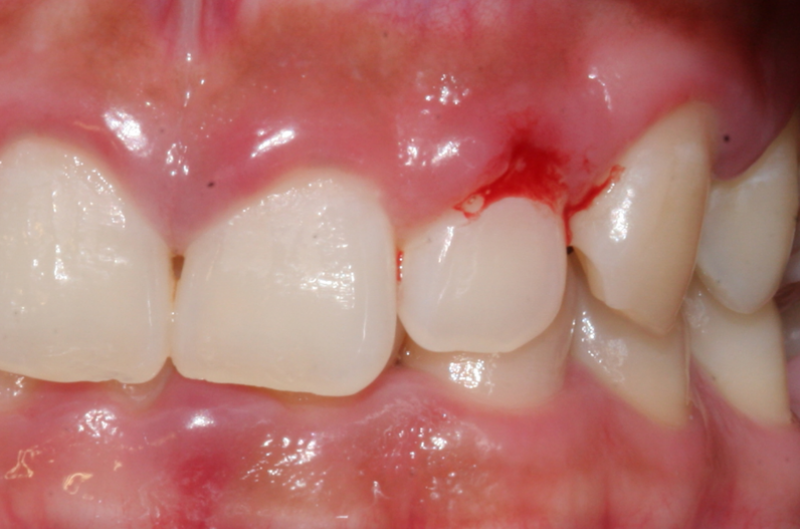

- 🩸 양치질 시 잇몸에서 피가 남잇몸이 약해지고 염증이 생기면 가장 먼저 나타나는 신호입니다.

- 🧼 잇몸이 헐거나 붉게 변화건강한 잇몸의 핑크색이 아니라 짙은 붉은색·자주색으로 변합니다.

치주염은 초기에는 별다른 통증이 없어 방치하기 쉽지만 진행되면 치아까지 잃을 수 있는 심각한 질환입니다. 양치 시 피가 나거나 잇몸이 붓는 증상이 반복된다면 치주염의 초기 신호일 수 있으므로 빠르게 진료받는 것이 중요합니다. 조기 치료가 치아를 지키는 가장 좋은 방법입니다.